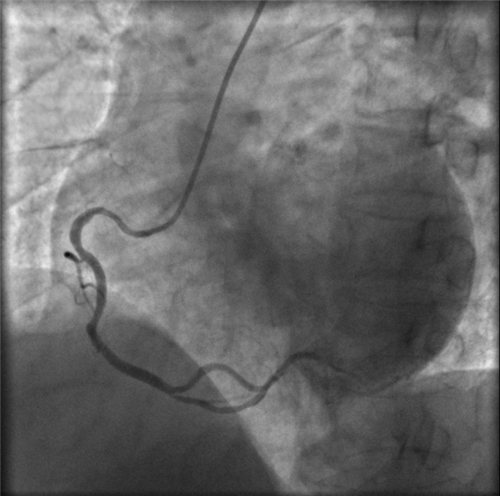

左主干完全閉塞

小心操作導(dǎo)絲及導(dǎo)管,艱難到達(dá)主動脈根部,但導(dǎo)管難以“到位”左冠口,“冒煙”見左主干居然完全閉塞了。